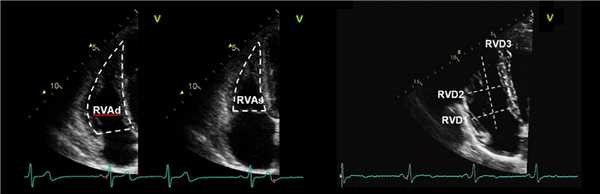

Измерения тела правого желудочка.

Все измерения должны быть получены в конце диастолы в апикальной 4-камерной проекции с фокусом на правый желудочек. RVD1: Базальный диаметр ПЖ — в базальной трети, RVD2: Средний диаметр ПЖ, измеренный на уровне сосочковых мышц ЛЖ. RVD3: длина ПЖ от плоскости трехстворчатого кольца до вершины ПЖ.